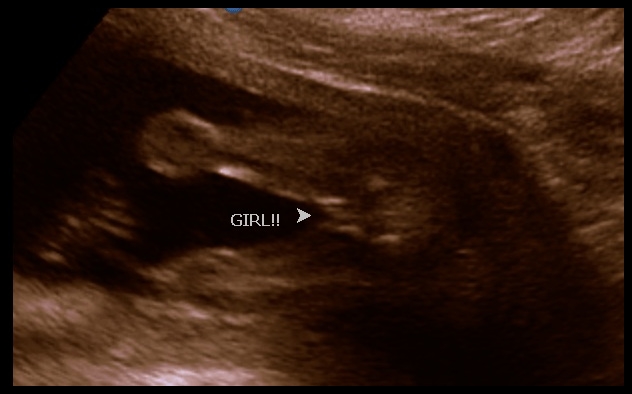

Faz o quê com a mãe que tinha o “feeling” que era menino? Que pecadiiinho com a minha princesa!!!

Tuuudo mentira aquelas crenças bobas, viu? Desde o começo da gestação eu tenho vontade de comer alimentos salgados e de beber sucos cítricos. A barriga, por enquanto parece mais pontuda do que redonda. Eu prefiro dormir virada para o lado esquerdo e não para o direito. Tudo isso, segundo a crença = MENINO!

Mas olha ELA aí! PEPECUDA LINDA!

Quando papai viu essa imagem na tela, deu aquele riso nervoso e disse ” ihhh, to pobre!” haha, não por ela, tadinha, talvez seja super econômica (nunca se sabe, né?) mas pela mãe dela que vocês conhecem 😛